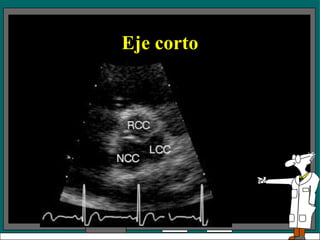

Eje Corto A nivel de la válvula aortica se puede observar:  Aorta, AI, AD, VD,  Válvula aórtica, con sus tres cúspides (derecha , izquierda y no coronariana), válvula pulmonar, válvula tricuspidea, septum IA, tronco de la arteria coronaria izquierda Permite identificar también el apéndice de la aurícula izquierda

Eje Corto Anivel de la válvula aortica se puede observar: Aorta, AI, AD, VD, Válvula aórtica, con sus tres cúspides (derecha , izquierda y no coronariana), válvula pulmonar, válvula tricuspidea, septum IA, tronco de la arteria coronaria izquierda Permite identificar también el apéndice de la aurícula izquierda